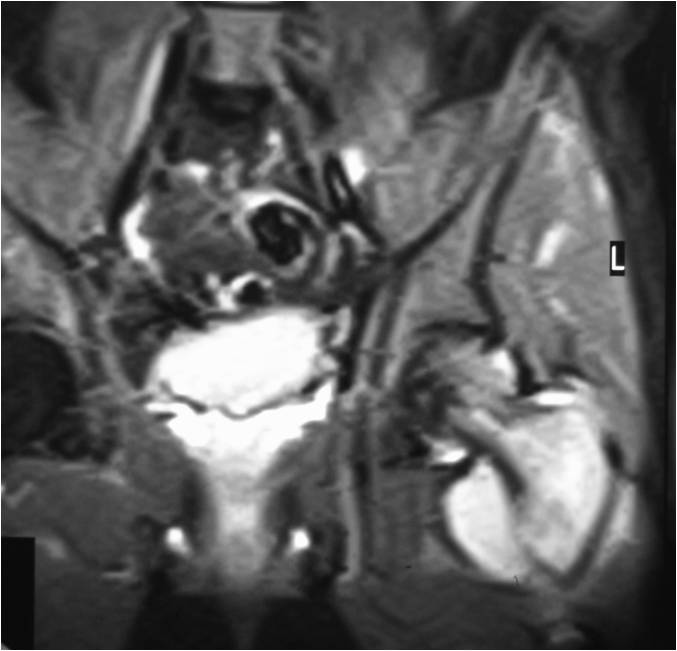

T2 Weighted MRI

- Soft tissue mass— by CT (80%); by MRI (100%)